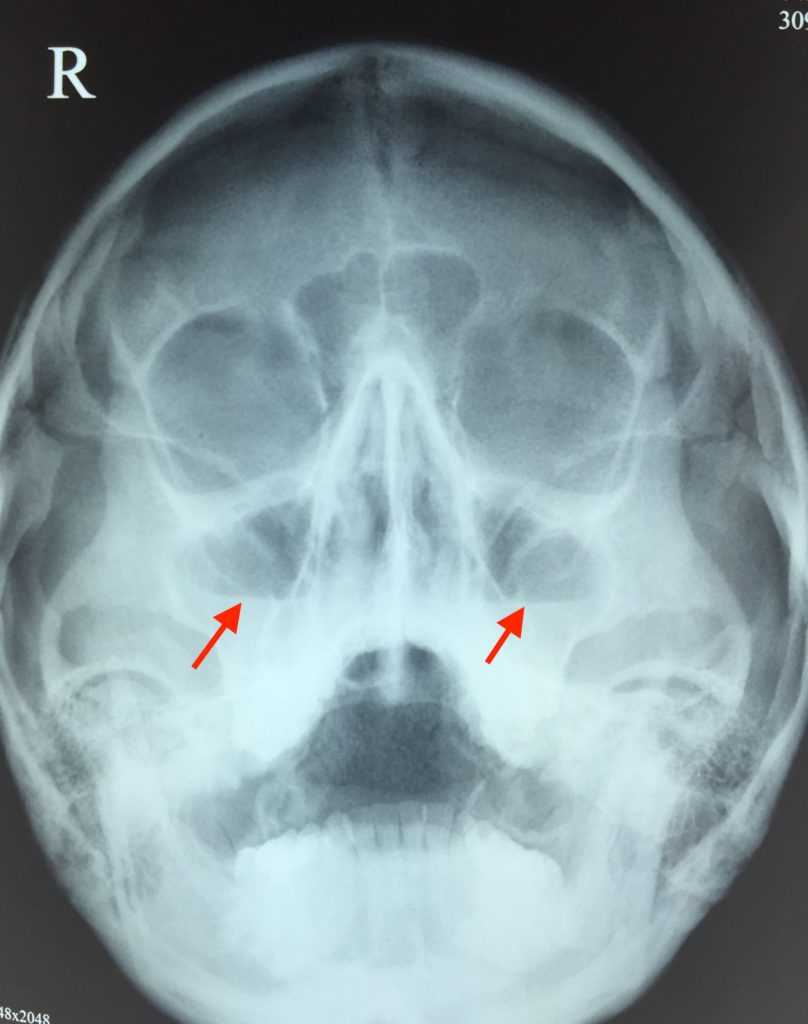

Гайморит на снимке имеет такие особенности:

- расхождение пазух с глазницами по цвету;

- неровные края, утолщенные стенки гайморовых пазух;

- инфильтрат;

- зоны белого цвета с четкой линией на фоне овального затемнения (так выглядит скопление жидкости);

- круги в пазухах с четкими границами и ровными краями (опухоли, кисты).

Рентген-снимок четко показывает: лобные пазухи, верхнечелюстные пазухи, решетчатый лабиринт.

Рентген пазух носа здорового человека выглядит так:

- Носовая перегородка разделяет носовую полость на симметричные стороны треугольника.

- Белые полосы, проходящие справа и слева разделенной области — это носовые ходы.

- Треугольные полости по бокам носа — гайморовы пазухи.

- Между глазницами расположена решетчатая пазуха с тонкими стенками, ячейки которой должны хорошо просматриваться.

- Выше глазниц определяются лобные пазухи, которые могут иметь различную форму. Допускается их разделение костными перегородками.

- В пазухах должен находиться воздух. Их края, как и контуры костей, должны быть четкими и ровными.

При воспалении верхнечелюстной пазухи рентген может показать специфические изменения слизистой оболочки, которые характерны для этого состояния. Оценить состояние синусовых полостей может только специалист данной области. Самостоятельное установление диагноза и лечение могут привести к серьезным, потенциально опасным последствиям. Чтобы понять, как определить воспаление верхнечелюстной пазухи на рентгеновском снимке, необходимо изучить анатомию этих полостей. Они расположены зеркально по обе стороны носа и представляют собой костные полости, выстланные тонким слоем слизистой оболочки. В нормальном состоянии синусы заполнены воздухом. Они соединены с носовыми ходами через специальное отверстие, через которое происходит обмен воздуха и дренаж слизи. В отсутствие патологий на рентгеновском снимке будет видно равномерное заполнение пазухи. Она будет немного темнее, чем кости черепа, имеет овальную форму с четкими контурами. Определить воспаление верхнечелюстной пазухи на рентгеновском снимке для опытного врача не составит труда. В результате воспалительного процесса в околоносовых полостях происходит отек слизистой, который может привести к перекрытию соединения с носовыми ходами. Это нарушает дренаж экссудата, что приводит к его скоплению в полостях. Рентгеновские лучи проходят хуже через жидкость, чем через воздух. На снимке при наличии воспаления отмечается затемнение верхнечелюстной пазухи, а также ее помутнение. Края полости становятся неровными, появляются уровни жидкости, отмечается полное или частичное отсутствие заполнения воздухом.

При остром катаральном верхнечелюстном синусите на рентгеновском снимке можно увидеть увеличение слизистой оболочки с образованием инфильтрации в нижней части пазухи, а также уменьшение воздушности. Кроме того, наблюдается отек слизистой оболочки синусового соустья и носовых ходов. Эти клинические признаки могут быть зафиксированы с одной или обеих сторон. Острый гнойный и серозный гайморит характеризуется полным или частичным отсутствием воздушности, отеком слизистой оболочки и наличием жидкости в полостях. Такое состояние требует немедленного медицинского вмешательства, включая прокол пазухи и установку дренажей. Гнойный процесс может повредить тонкую костную ткань и проникнуть к мозговым оболочкам, что может привести к серьезным осложнениям. На рентгеновском снимке хронического гайморита можно увидеть увеличение слизистой оболочки, ее разрастание и наличие новообразований, таких как кисты и полипы. При обострениях наблюдается специфическая картина, характерная для острого синусита.